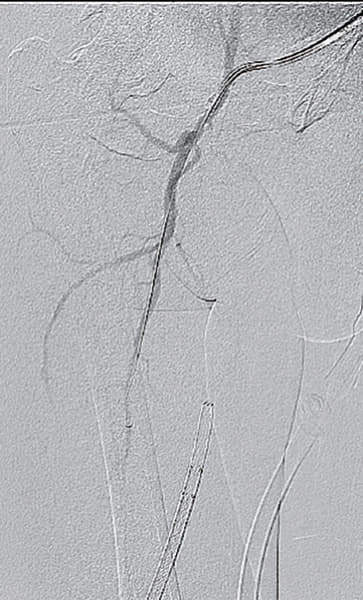

- SFA起始部にわずかなstumpを認め、膝窩動脈のP1-segmentまで連続する閉塞病変あり(図1)

- 4 Fr IMA(内胸動脈用)造影カテーテル併用し0.014 inch wireを閉塞内へ進入し、ステント近位まで比較的容易にワイヤリングすることに成功(血管内超音波(IVUS)にてintra-plaqueであることを確認)